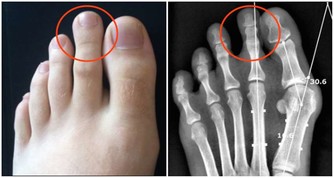

4肝功能反常

當血糖濃度下降時,肝不能做出準確的反應,來分化肝醣元來維持正常的活動能量。於是持續耗費血液中不多的糖元,形成越來越重的生理反應——餓,煩心的餓。